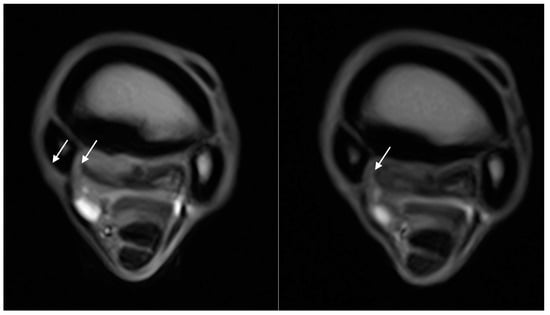

3. Results